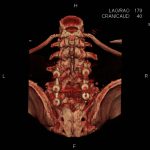

- Empiemul subdural

- Abcesul cerebral

- Fistula carotido-cavernoasa

- Higroma

- Atrofia cerebrală regională